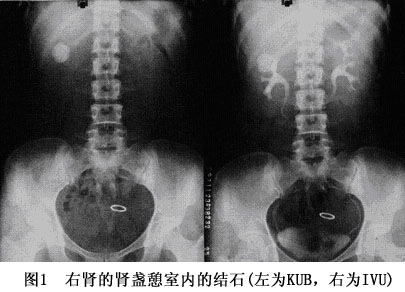

(2)排泄性尿路造影:排泄性尿路造影除了可以进一步确认在X线平片上不透X线阴影与尿路的关系外,还可见患侧上尿路显影延迟;肾影增大;肾盂及梗阻上方的输尿管扩张、迂曲等改变,并据此了解肾脏的功能情况。必要时需延长造影的时间以求患侧满意显影。对输尿管壁段的结石,充盈的膀胱影可掩盖结石的影像,此时可嘱患者排尿后再摄片。可透X线的结石在IVU片上可表现为充盈缺损。通过IVU片还可以了解肾脏的形态、有无畸形等情况。通过IVU还可显示出肾盏憩室的结石与集合系统的关系(图1)。